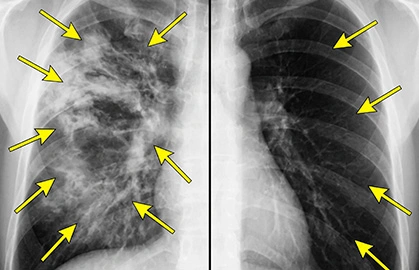

NBC EXCLUSIVE: Snoop Dogg Confirms Sam Elliott's 17-Day COPD Breakthrough - The At-Home Method Helping Thousands Breathe Easy Again

A Harvard-trained physician exposes the hidden link between common inhalers and blocked airflow - and reveals a simple "valve-reset" routine that's helping thousands breathe easier in just 17 days.

Early users say they feel like their lungs finally opened up - and wish they'd found this sooner. Watch the full NBC report now before it's taken down - and discover what could be quietly making your symptoms worse.